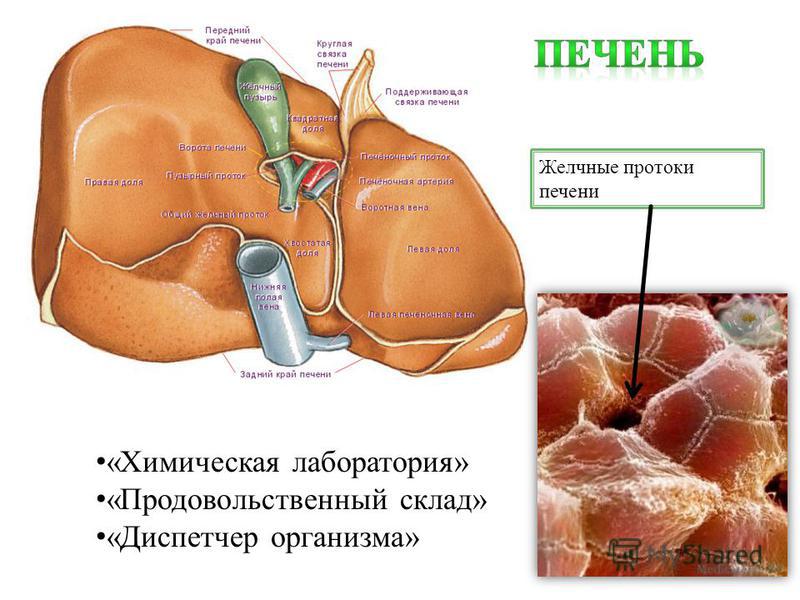

Анатомия и особенности Гартманова кармана желчного пузыря